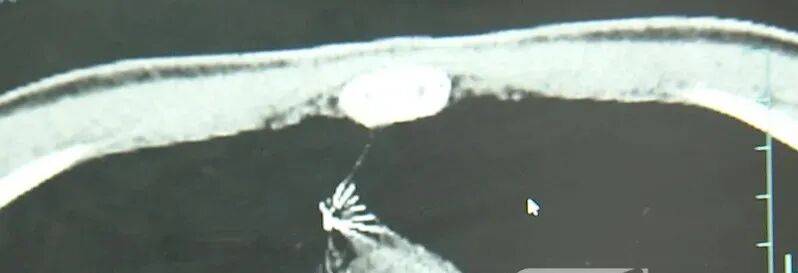

近日,安徽17岁小伙小陆参加征兵体检,胸片结果显示:胸腔内有一处金属高密度影,形态细长,像一根针梅雁吉祥股票。

进一步的CT检查确认,异物是一枚金属针,斜插在肺组织内,位置十分凶险梅雁吉祥股票。

杭州市第一人民医院心胸外科副主任冯兴说:“我们看到这个针的尖锐部,正好指向他体内的一个大血管,边上是上腔静脉和胸主动脉,因此这个针稍有不慎,就有可能造成周边血管的损伤,甚至危及生命梅雁吉祥股票。”